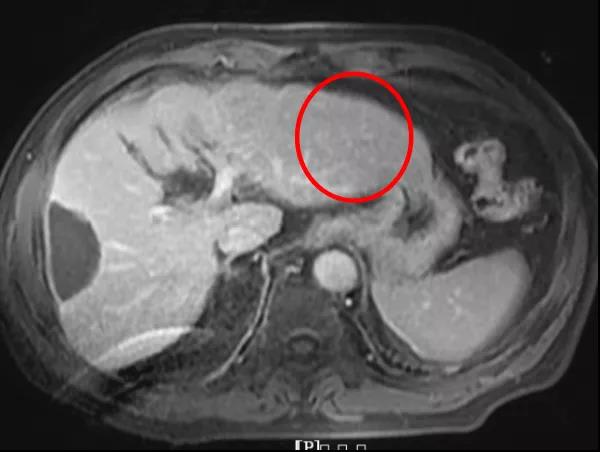

(2)联合治疗6周期

疗效评价:CR。

本例患者经替雷利珠单抗联合靶向治疗至今,肝内靶病灶完全消失,AFP也由治疗前的615 ng/ml降至正常(6.8 ng/ml),总体疗效评价达到CR。患者用药至今PFS已超过6个月,除轻度的血小板下降之外,无其他不良反应事件发生。因此,对于ECOG PS评分0~1分、Child Pugh A级等身体基线情况比较好的患者,首次用药时就可以同时联合使用免疫和靶向药物,安全性良好,获益持久。替雷利珠单抗作为肿瘤治疗领域引领突破的PD-1单抗,强强联合一线靶向药物,未来或将成为晚期HCC治疗优选之一,为患者赢得更多生命延长的机会。